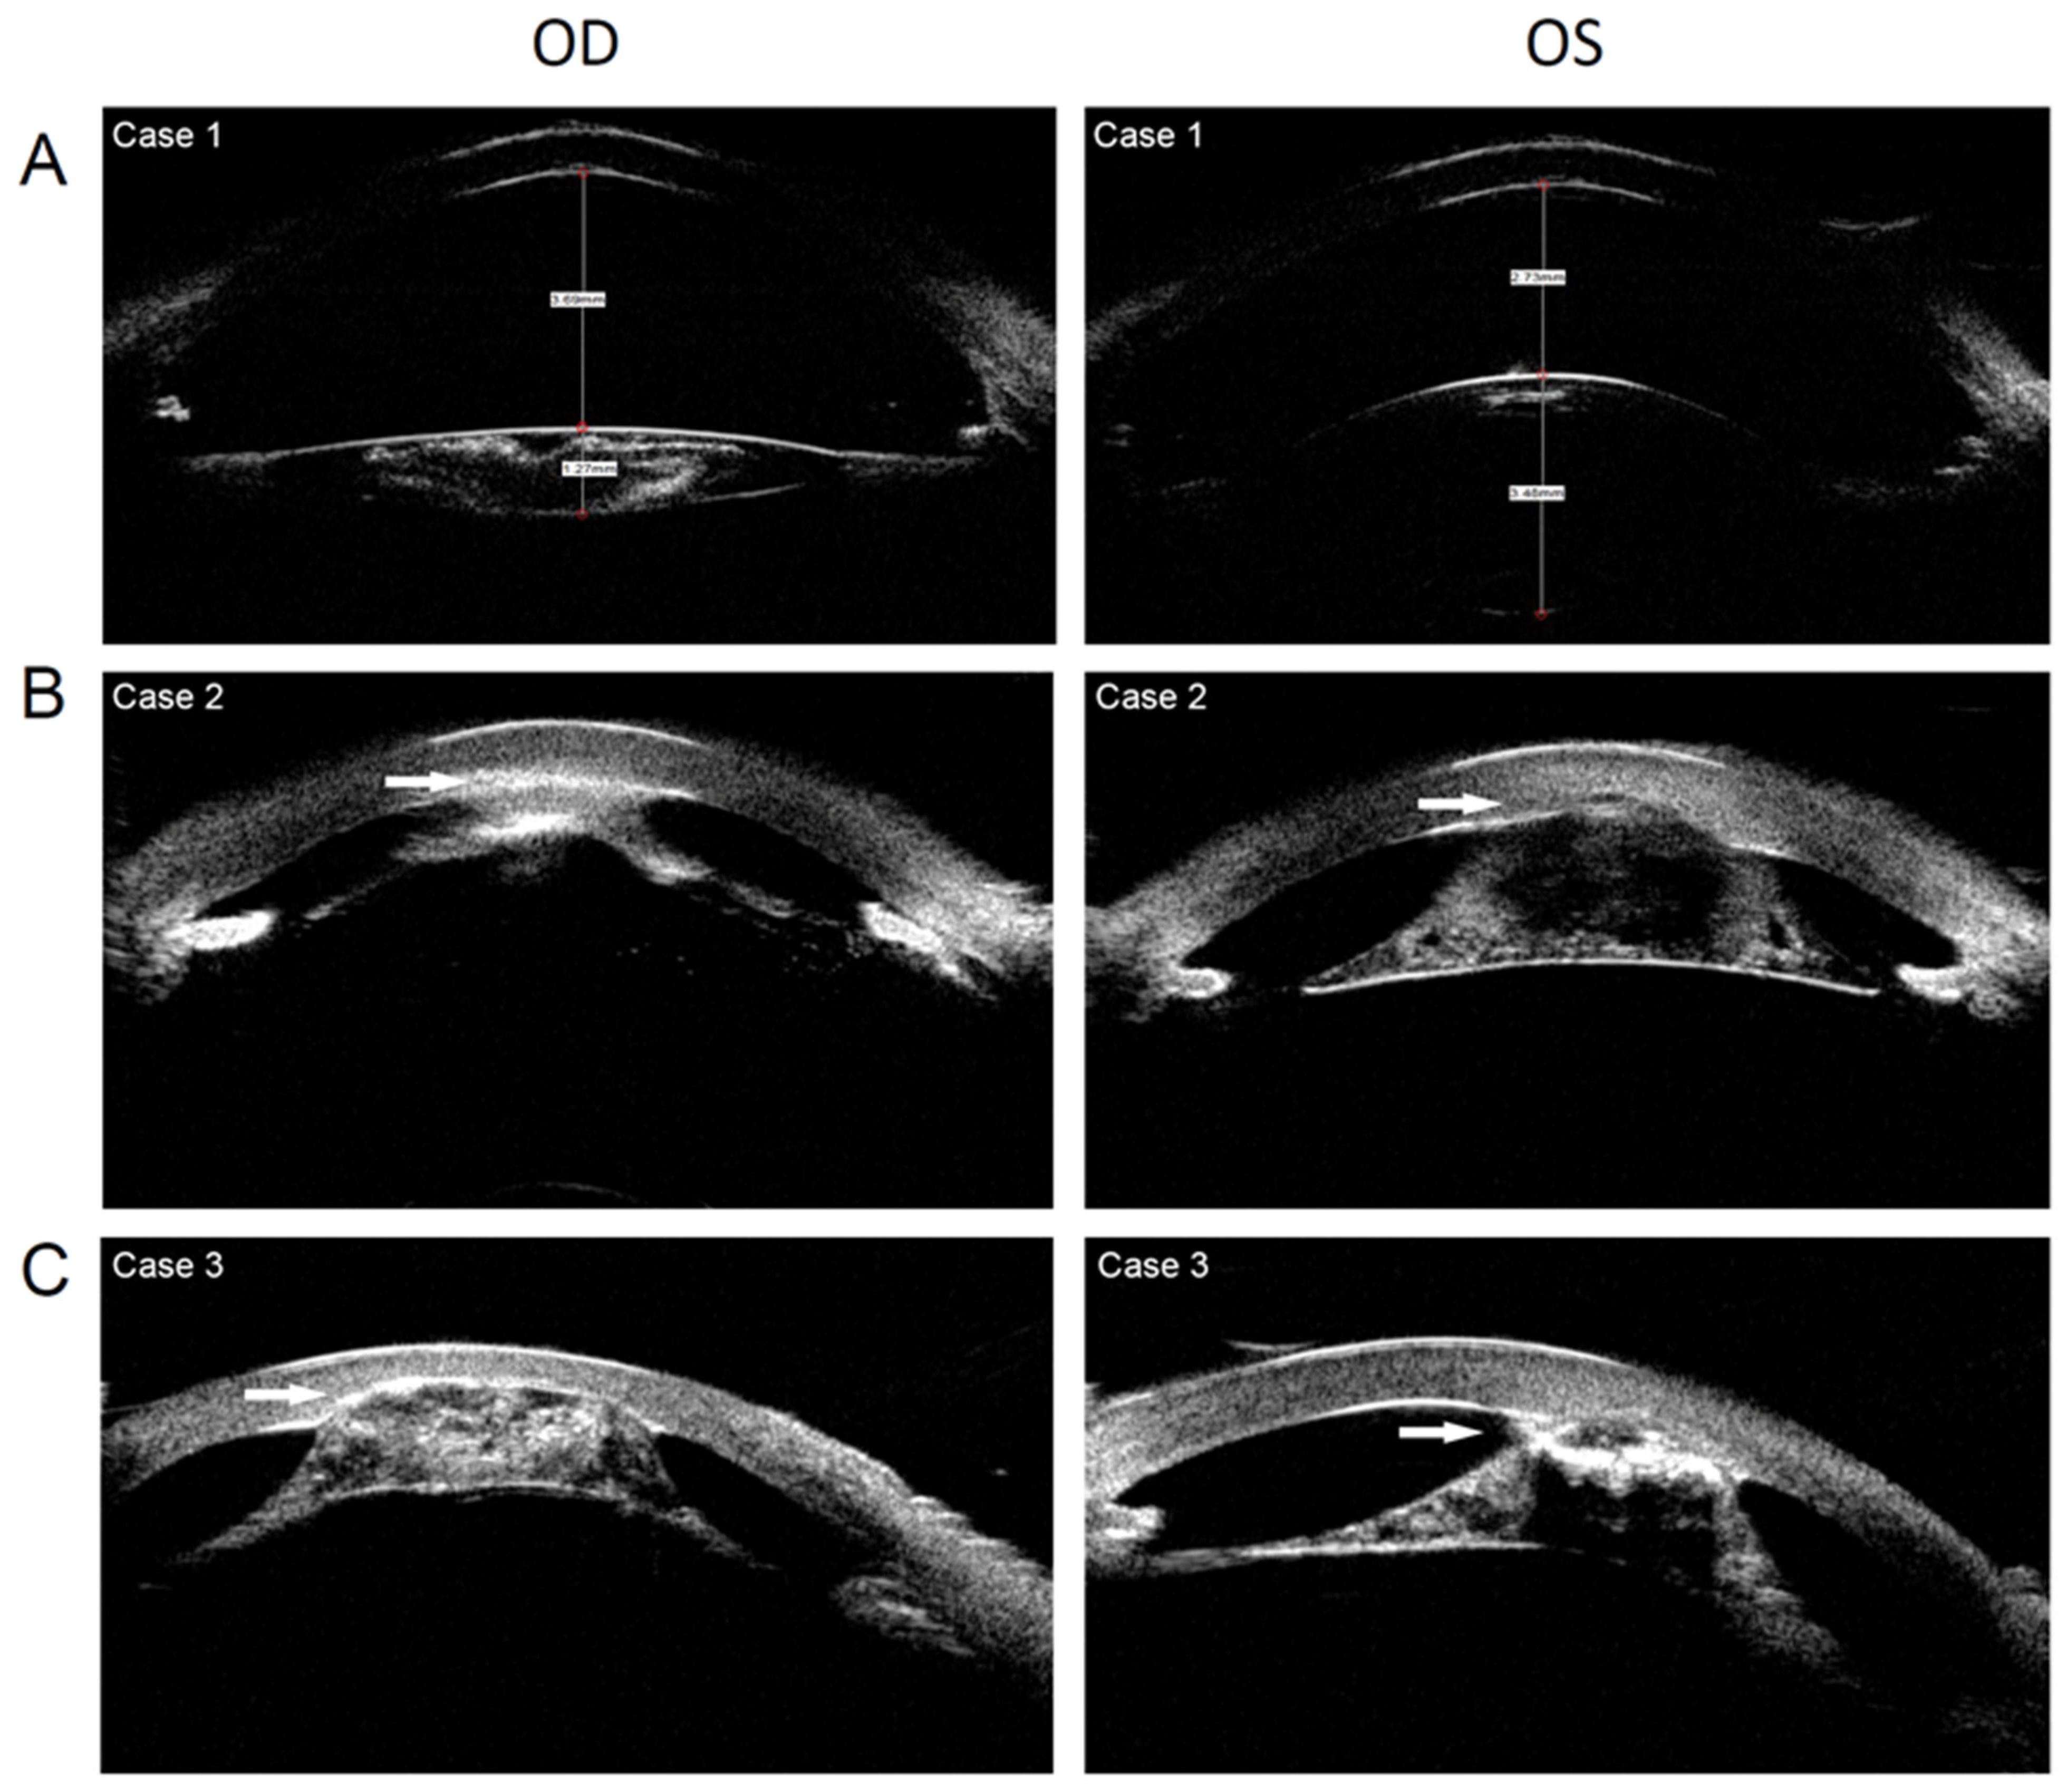

Figure 3. Ultrasound biomicroscopy of 3 patients with WAGR syndrome. (A). Anterior segment of case 1 showing the thin lens of the right eye and aniridia of both eyes. (B). Anterior segment of case 2 showing keratolenticular adhesion, aniridia, and thin lens. (C). Anterior segment of case 3 showing keratolenticular adhesion, aniridia, and thin lens. (White arrow: keratolenticular adhesion).

An 11-month-old girl presented with whitish pupils, and nystagmus was noticed by her parents at birth. A further examination found a thin lens with nuclear opacity of the right eye, normal thickness, posterior cortical cataract of the left eye (Figure 2A and Figure 3A), a cup-to-disc (C/D) ratio of 0.6, aniridia, and macular hypoplasia in both eyes (Figure 4A,B). The intraocular pressure (IOP) was 15.3 mmHg in the right eye and 16.2 mmHg in the left eye, as measured using a Tono-Pen (Reichert, Inc., Depew, NY, USA). The axial lens (AL) was 22.24 mm in the right eye and 22.98 mm in the left eye. She underwent uneventful bilateral nephron-sparing surgery due to Wilms tumor. Developmental delay was also diagnosed. CNV analysis based on WES found a deletion of Chr11:19372477–35827981. WAGR syndrome was confirmed. Ocular surgery was not prescribed. Twice-a-year follow-up was scheduled. At the 1-year follow-up, the middle of the nuclear opacity of the right eye had been spontaneously absorbed (Figure 2B). The IOPs of both eyes were normal, and the tumor did not recur or metastasize.

A 23-month-old girl presented with bilateral whitish cornea, and nystagmus was noticed by her parents at birth. A slit-lamp examination showed keratolenticular adhesion (the anterior surface of the thin lens adherent to the posterior surface of the cornea), corneal neovascularization, aniridia, and a thin lens with nuclear and bubble-like opacities in both eyes (Figure 2C and Figure 3B). An OCT examination revealed macular hypoplasia in both eyes. The AL was 16.63 and 17.07 mm in the right and left eyes, respectively, indicating nanophthalmos. The IOP was 16 mmHg in the right eye and 35 mmHg in the left eye, as measured using a Tono-Pen. The IOP was controlled using ocular IOP-lowering medications. The girl underwent uneventful right kidney resection due to Wilms tumor. An atrial septal defect and developmental delay were also diagnosed. A CNV analysis based on WES found the deletion of Chr11:26210680–35006316. WAGR syndrome was confirmed. Ocular surgery was not prescribed. Twice-a-year follow-up was scheduled. At the 1-year follow-up, the ocular disease had not deteriorated further, and the tumor did not recur or metastasize.

An 18-month-old boy presented with bilateral whitish cornea, and nystagmus was noticed by his parents at birth. Slit-lamp examination showed keratolenticular adhesion, corneal neovascularization, aniridia, and a thin lens with nuclear and bubble-like opacities. The anterior surface of the lens was adherent to the posterior surface of the cornea (Figure 2D and Figure 3C). An OCT examination indicated macular hypoplasia. The IOP was 18 mmHg in the right eye and 17 mmHg in the left eye, as measured using a Tono-Pen. Wilms tumor and developmental delay were diagnosed when the boy was 15 months old. He underwent uneventful left kidney resection and postoperative radiotherapy. A CNV analysis based on WES found a Chr11:30032154–36680772 deletion. WAGR syndrome was confirmed. Ocular surgery was not prescribed. Twice-a-year follow-up was scheduled. During the 2-year follow-up, the IOP of the child was normal, the ocular disease did not deteriorate, and the tumor did not recur or metastasize.